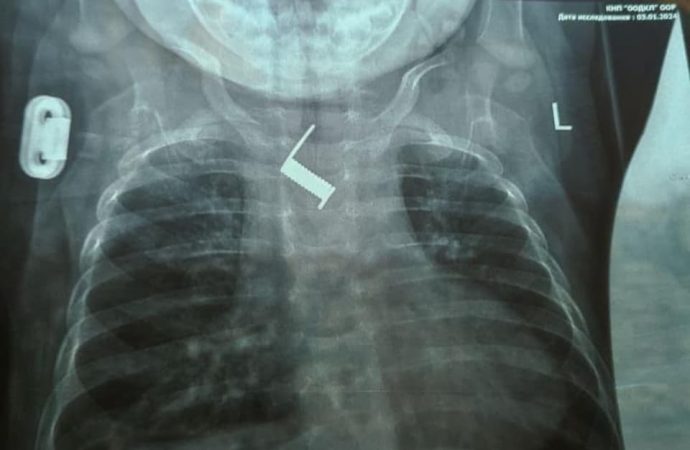

При поступлении в стационар в ООДКБ ребенку провели обзорную рентгенограмму, во время которой обнаружили инородное тело — пружинка от шпильки для волос.В отделении инструментальных методов исследования и лечения Одесской областной детской клинической больницы с помощью эндоскопии было удалено инородное тело в пищеводе.

За это время инородное тело почти вросло в стенку пищевода и находилось на уровне средней трети пищевода, рядом с дугой аорты.